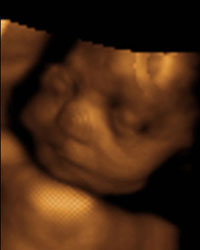

March 9th, 29wks.

This was a purely fun appointment. We did the 4D ultrasound and got to see Ella in better detail and real-time movement. She's a chubby little baby too. Well rounded little cheeks, and she was really working that mouth... sticking out her tongue at us. The technician kept trying to get pictures of her doing that but by the time the picture was taken her mouth was closed again. She was still for the first half, and her hands must've been tucked underneith her so that we got lots of clear shots of her face. Then for the last half she was really moving around. Looked like she was working on her boxing moves. The technician said that she was a very photogenic baby. :) She was cute. And without further delay, here she is!!